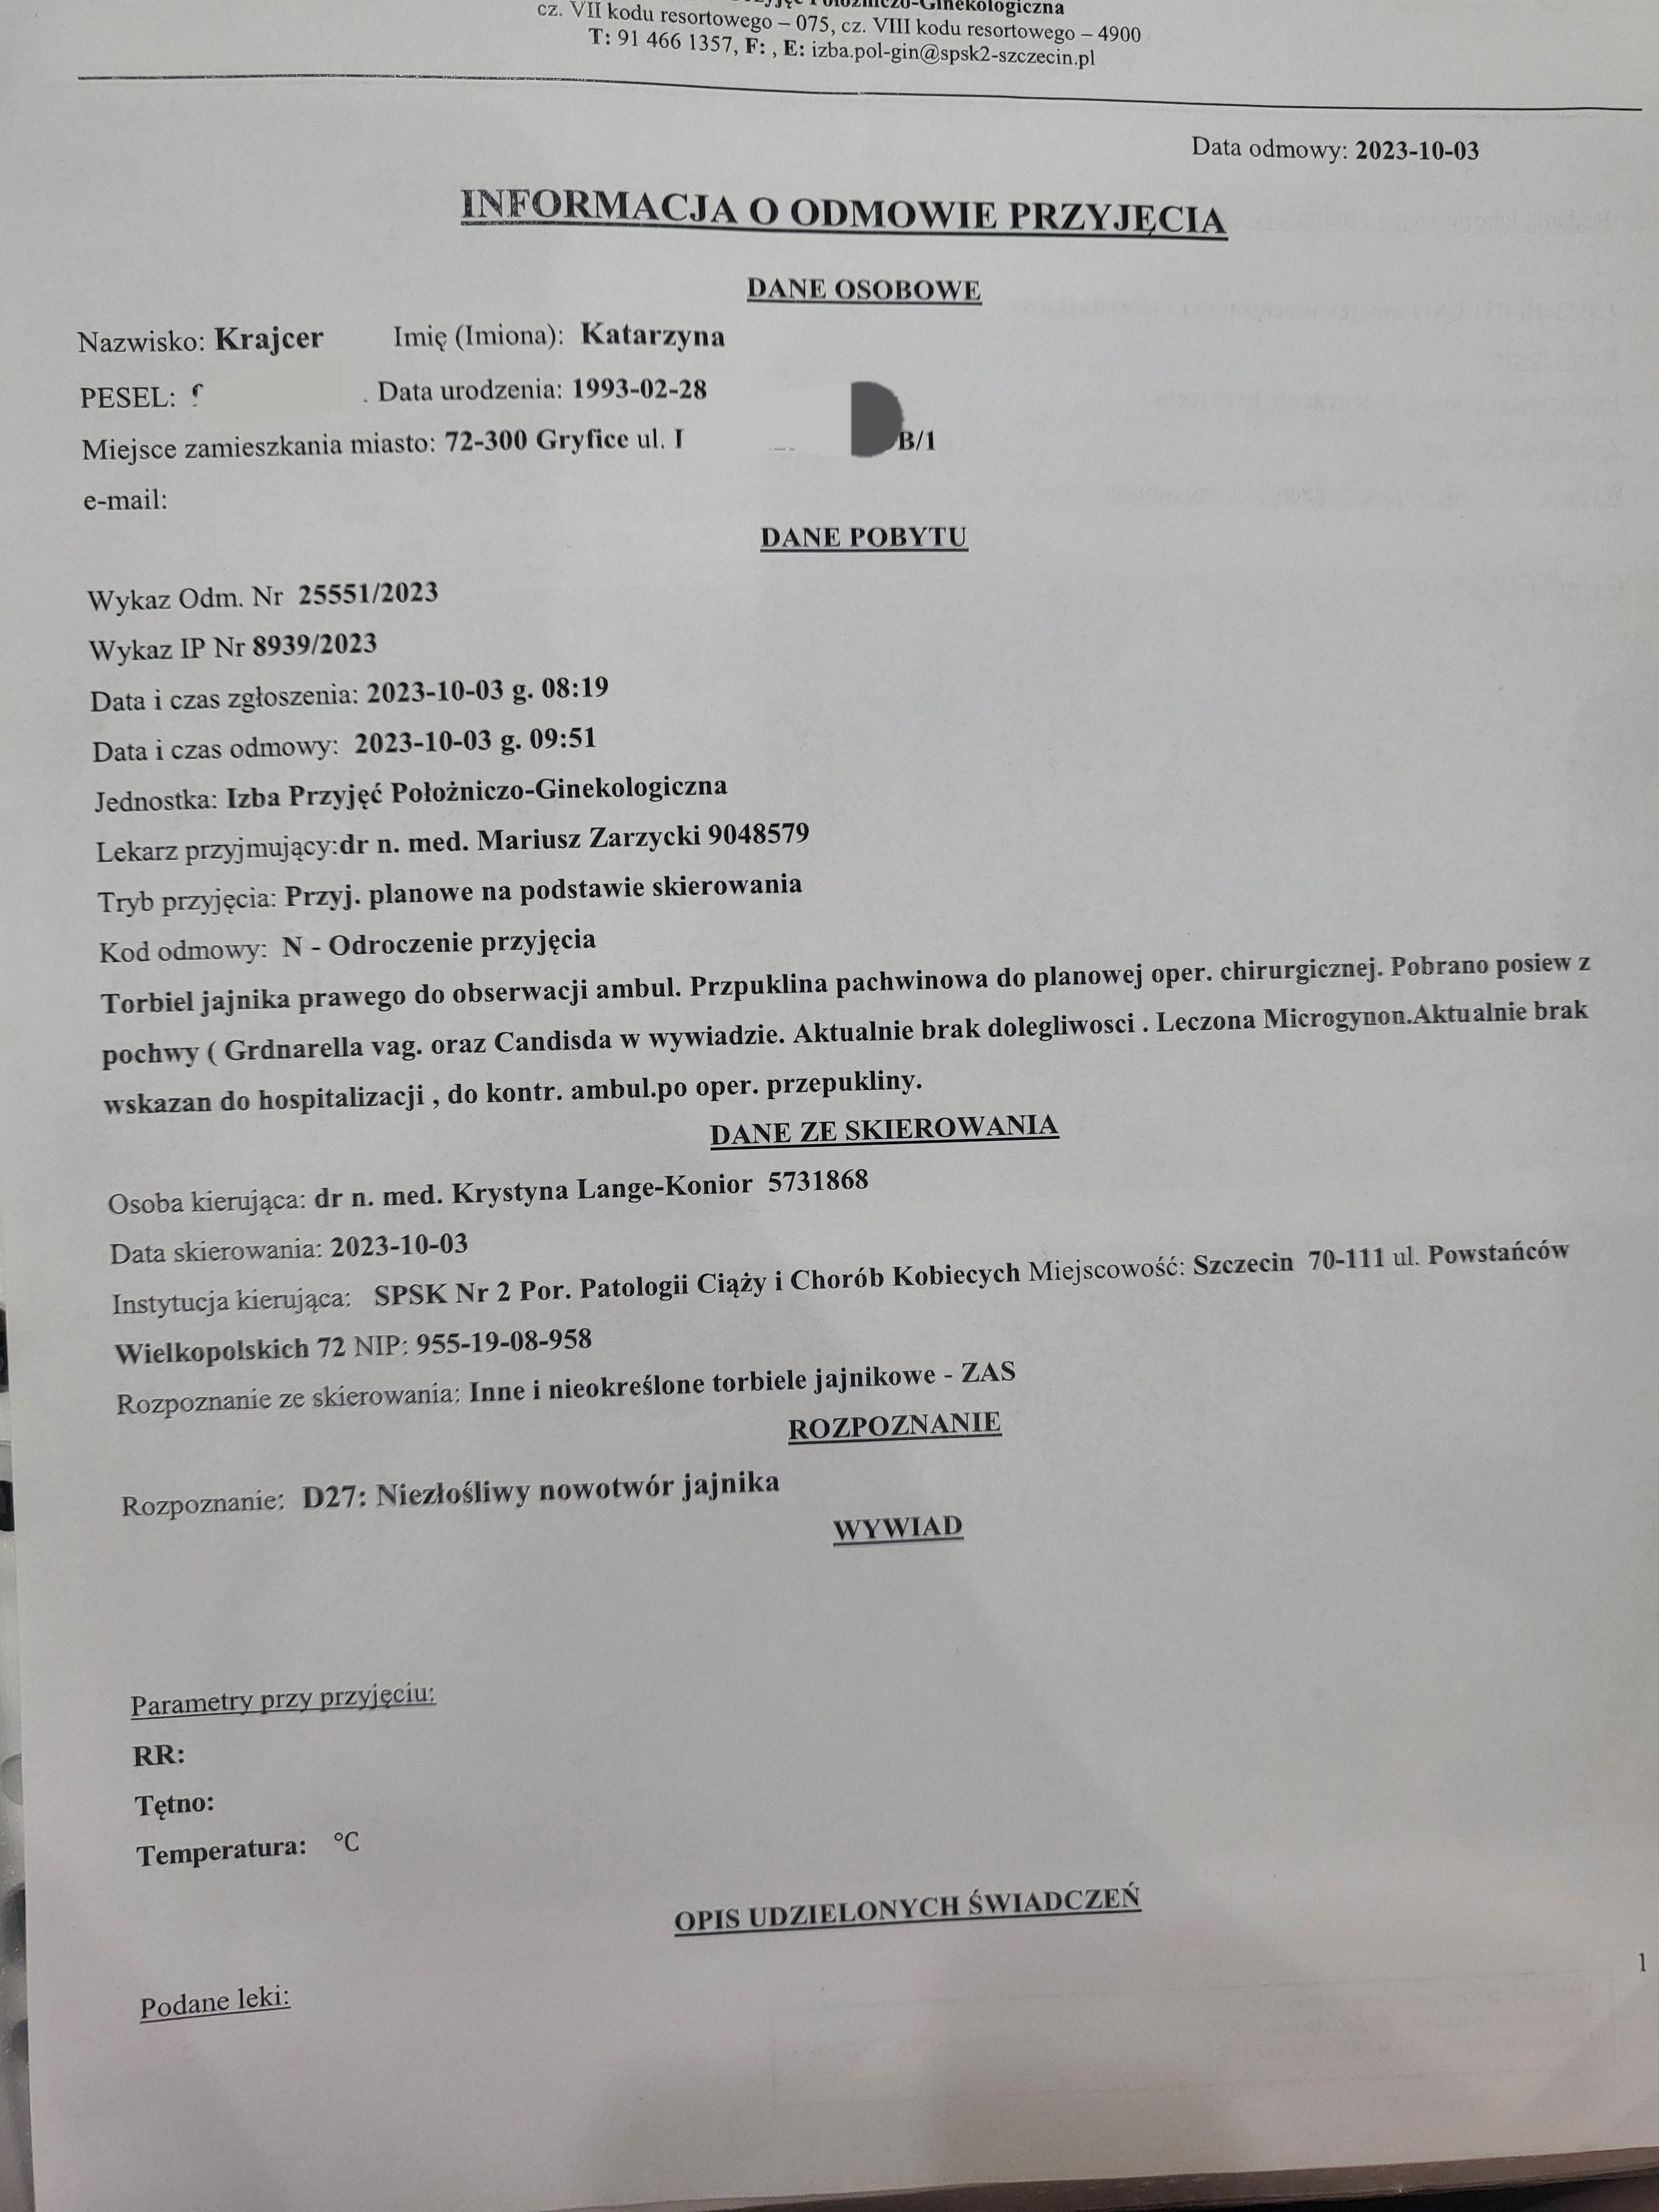

Pani doktor przy każdym USG transwaginalnym odnajdywała torbiele: mniejsze, większe, mnogie, dwukomorowe – lecz były ,, do obserwacji”. Pomimo przyjmowania tabletek hormonalnych one nadal się pojawiały. W celu diagnozy skierowano mnie na laparoskopię, która się nie odbyła ze względu na planowaną w niedługim czasie operację usunięcia dwóch przepuklin pachwinowych.

Zrozpaczona udałam się na konsultacje do jeszcze dwóch innych ginekologów, którzy mówili niemalże jednym głosem ,, bierze pani tabletki hormonalne i nie powinno być ani jednej torbieli” .

Natychmiast umówiłam się na wizytę, która potwierdziła obecność torbieli. Dostałam po raz kolejny nic nie wnoszącą radę ,, trzeba obserwować”.